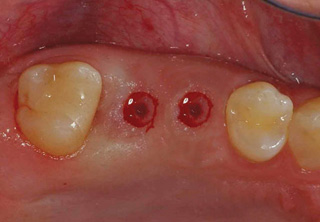

치조골 이식술 전후사진

B

A